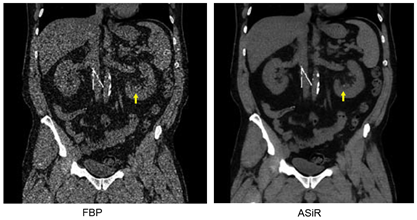

图1. CT成像与几何采样示意图 CT迭代重建技术的基本原理是:首先通过滤波反投影技术(FBP)获得重建图像,这是对重建物体的第一次估计,但存在较大误差。然后对CT扫描和数据采集过程进行数学建模,将第一次通过FBP得到的被扫描物信息代到模型之中,通过计算得知第一次估计的物体经过CT扫描,探测器应该得到的数据信息,并将该计算得到的信息与实际CT扫描中探测器的数据信息进行对比检验,根据两者的区别,对第一次估计进行校正,得到第二次估计,再将第二次估计代到模型之中,进行检验。如此通过反复迭代的方式,对重建物体进行不断校正,直到通过模型计算得到的信息与探测器真实的信息吻合,得到最终的重建图像。 我们可以通过手电筒实验来加深对迭代重建技术原理的理解,迭代技术相当于根据手电筒从不同角度对物体的照射图像,获得对第一次对物体的估计,然后根据第一次对物体的估计,并假设这样一个的物体放到实验条件中,通过虚拟的手电筒照射,我们的眼睛应该看到什么样的图像,将该虚拟的图像与真实的图像进行对比。根据两者的区别,对被估计物进行校正,将校正之后的物体,再通过假设进行第二次估计和校正......直到最终被估计的物体虚拟的图像,与实际眼睛看到的图像一致,我们最终获知了容器中装得是什么物体。 2008年,GE公司首先推出基于系统统计模型的统计迭代重建技术(ASiR)。ASiR重建技术通过首先建立噪声性质和被扫描物体的模型,并利用迭代的方法对噪声加以校正和抑制, 得到更清晰的图像(图2)。ASiR技术可以显著降低重建图像的噪声,改善图像质量,与FBP算法相比,降低大于50%的扫描剂量,并提高了密度分辨率。目前ASiR技术配置在GE生产的超高端能谱CT、高端128层CT和16排50层CT,不仅可用于常规CT扫描,也可用于心脏扫描和能谱扫描。

图2,左肾结石CT成像FBP和ASiR重建技术对比 继第一代ASiR迭代重建技术推出并取得良好的临床应用之后。2011年,GE公司推出多模型迭代重建技术(Model-Based Iterative Reconstruction, MBIR, 商品名VEO)。与ASiR重建技术不同的是,MBIR技术除了建立系统统计模型之外,还建立了系统光学模型,对体素、X射线光子初始位置和探测器几何因素均通过模型进行模拟,真实地还原了X射线从投射到采集的过程(图3)。